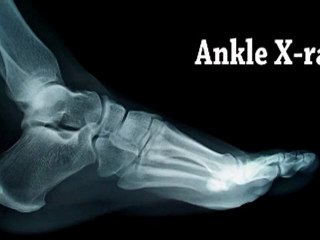

Ankle Sprains - Podiatrist in Bethesda, MD and Springfield, VA br Dr. Paul Ross discusses the symptoms, causes and treatments for br br br Ankle sprain is caused by an unnatural twisting or force on the ankle bones of the foot, which may result in excessive stretching or tearing of one or more ligaments on the outside of the ankle. The severity of the sprain can impact the degree of damage as well as the type and duration of treatment. If not properly treated, ankle sprains may develop into long-term problems. br Primary symptoms of ankle sprains are pain following a twist or injury, swelling, and bruising.